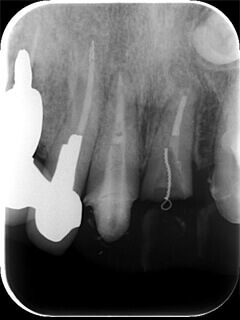

症例2 レントゲンで見てもしっかり治療が終わっているのにまだ疼く

マイクロスコープで小さい神経を見落とさない。

歯の神経は非常に細いため肉眼ではたびたび神経を見落としてしまうことがあります。

(この症例ではMB2という細い神経を見つけることができました)

7

矢印の部分にわずかに小さい穴が見えます。

8

拡大すると見逃していた神経が現れ膿が出てきました。そこを綺麗にすると疼いていた症状が無くなりました。